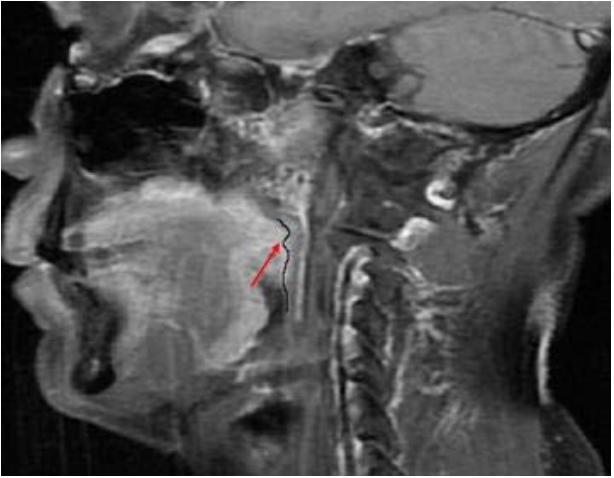

79. 之拍攝方式為何? (A)核磁共振(magnetic resonance imaging) (B)電腦斷層(computerized tomography) (C)同位素骨掃瞄(radioisotope bone scan) (D)超音波掃瞄(ultrasongraphy)

80.承上題,此影像所顯示右側腮腺(parotid gland)之病變,最可能之診斷為: (A)良性腫瘤 (B)黏液囊腫 (C)淋巴結鈣化 (D)唾液腺結石